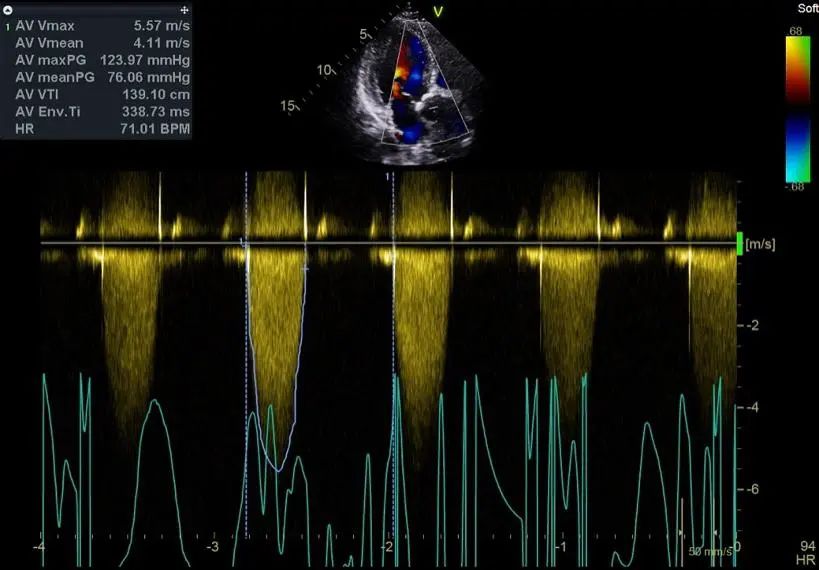

动态心电图示频发房性早搏伴短阵房速。肺功能检查提示轻度阻塞性通气功能障碍。头颅MRI未见明显脑梗征象。入院后食道超声提示该患者为主动脉瓣二瓣化畸形、重度狭窄伴轻度关闭不全。峰值流速5.57m/s,最大跨瓣压差124mmHg,平均跨瓣压差76mmHg,瓣口面积为0.41cm2。

多普勒超声显示其流速和压差达重度狭窄